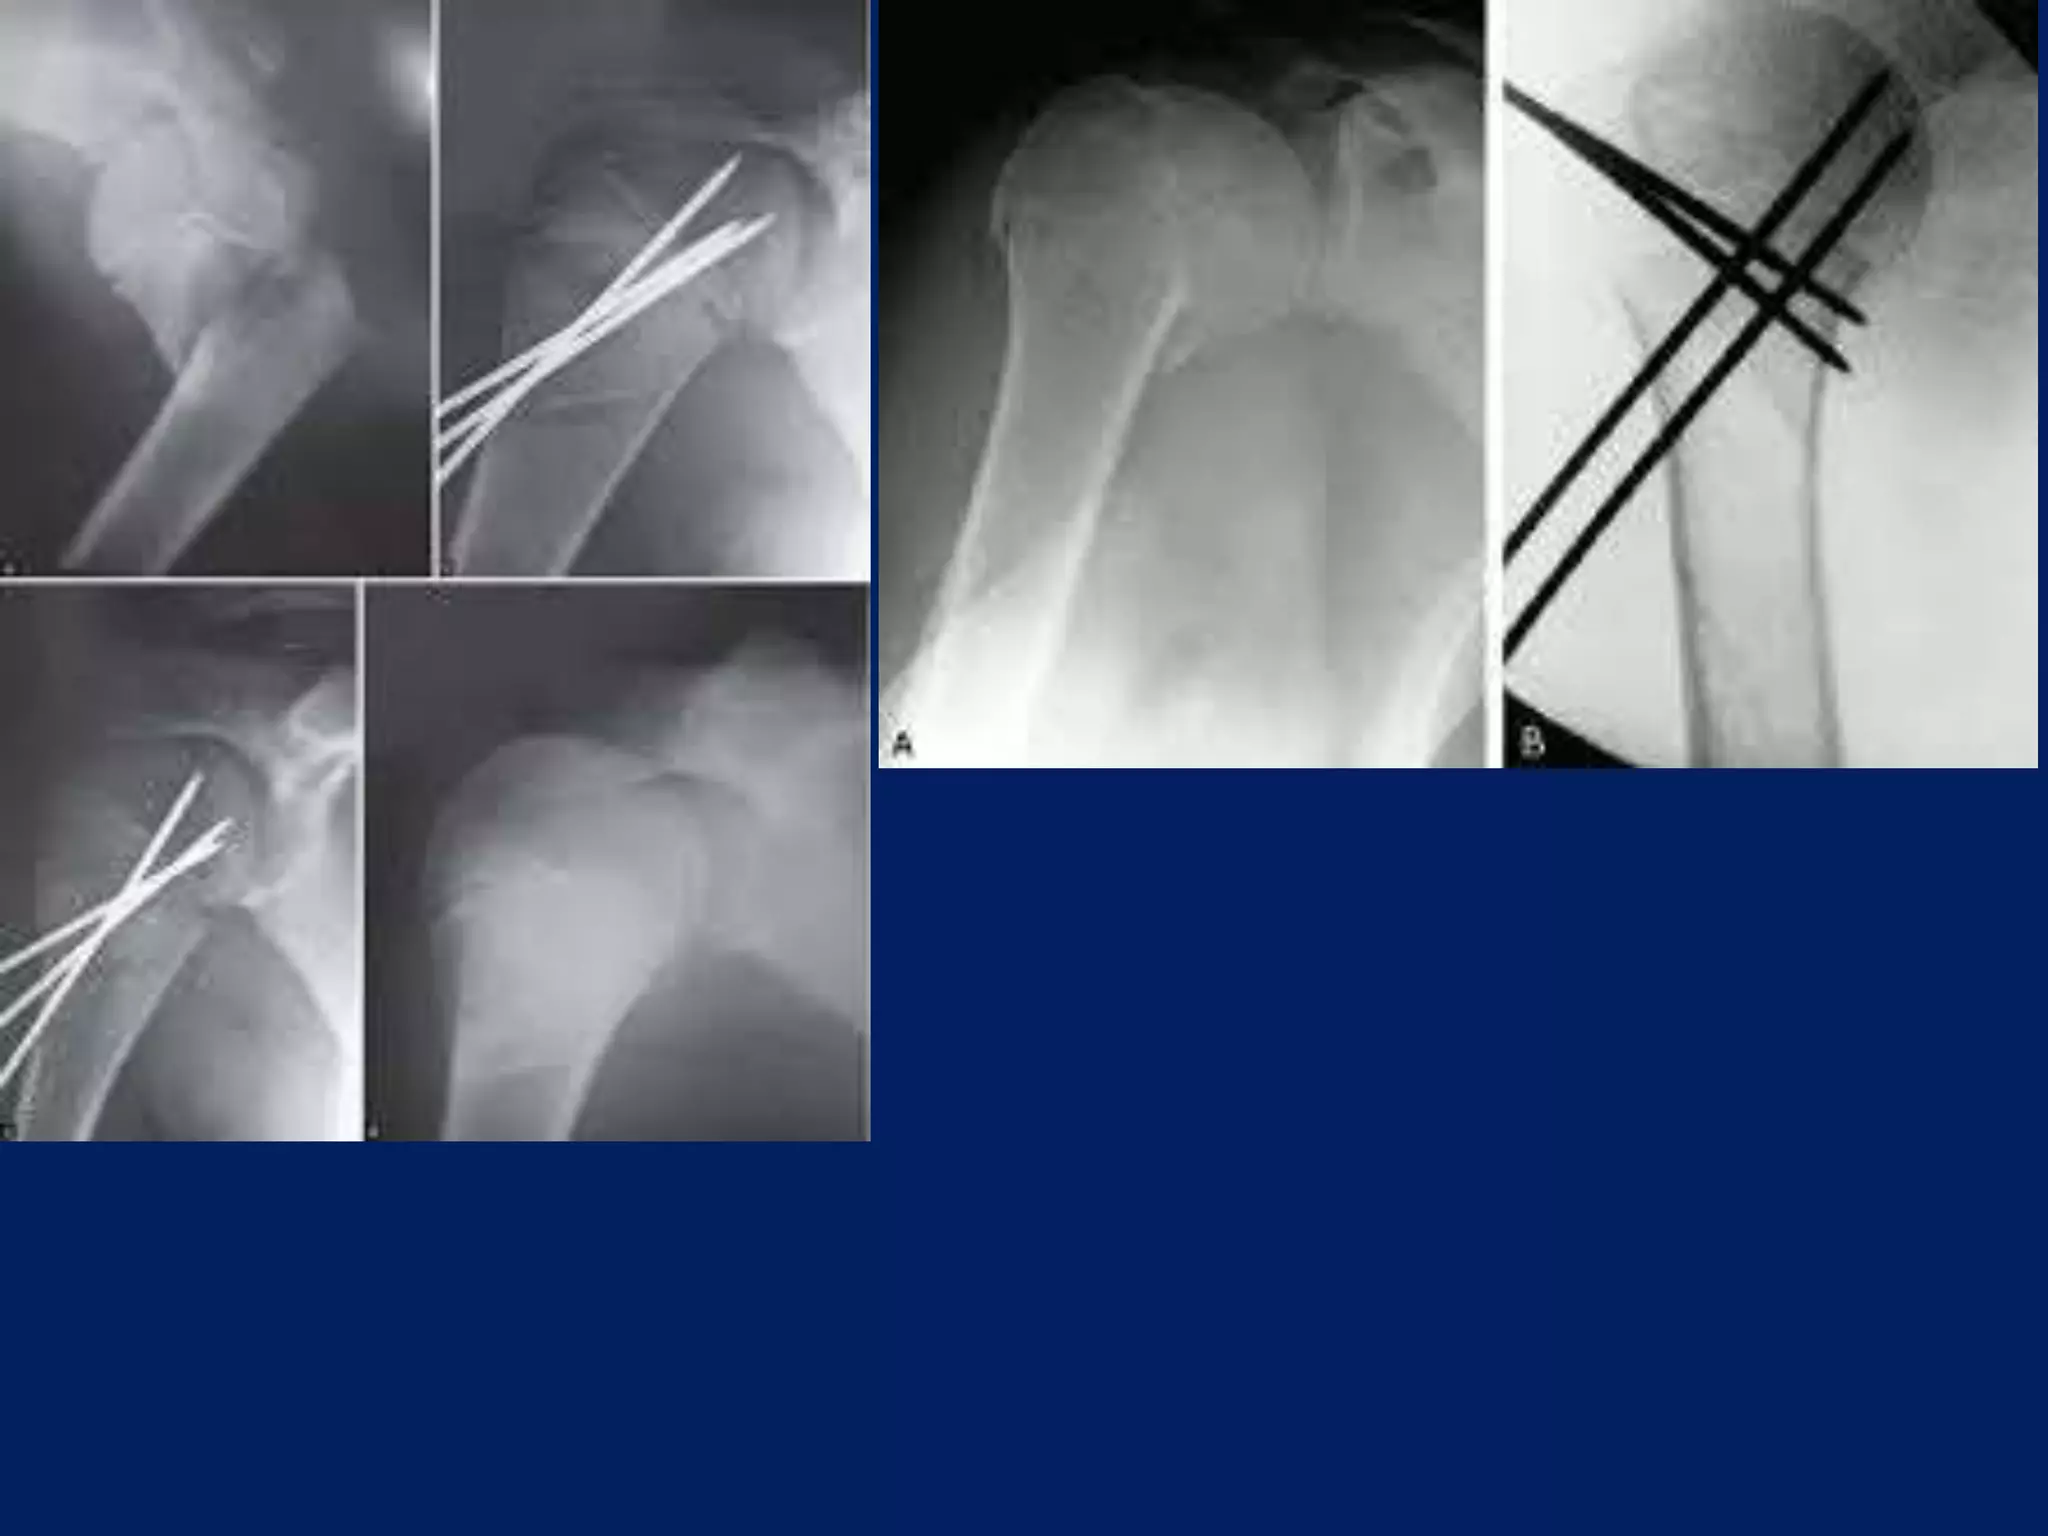

Operative contd... • 2.5mmSchanz pins/ K wire at humeral head at 300 to each other in horizontal plane. • 1st: In true lateral/ coronal plane 2nd: just lateral to bicipital groove 3rd: 300 posterior to 1st one.

A displacement ofGreater tuberosity superiorly may cause Impingement. A displacement posteriorly can cause External rotation is blocked.

• Next 2.5mmpin inserted in coronal plane in line with 1st pin, approximately 4cm or 3 finger/ below the 1st pin in upper third of Humerus. • 3rd pin placed 2cm below the above pin laterally. • Wires are placed from lateral cortex to medial cortex into the head upto the subchondral area

Operative contd... • Nowthe wires are joined through Link joints of JESS and a curved rod.

• A wirecan be placed from the head to bring down the head as near to the shaft.